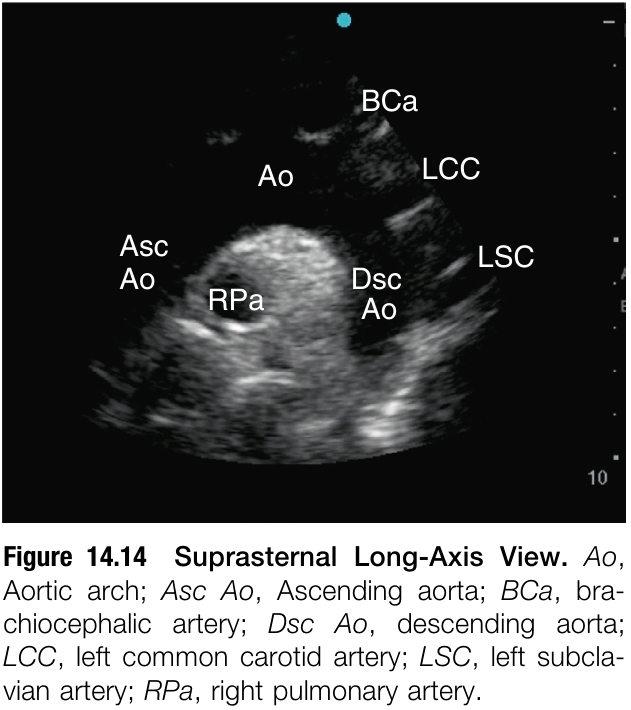

SUPRASTERNAL WINDOW

Supraternal imaging은 routine하게 시행하지 않지만, suprasternal window로 aortic arch를 볼 수 있으므로 point-of-care context에서 acute aortic pathology의 빠른 확인이 가능하다. 환자는 supine position을 취한 뒤 neck을 extension 한다. Trnasducer를 suprasternal notch에 댄 후 transducer oritentation marker과 환자의 left shoulder를 보게 하고, inferior 쪽으로 tilting 해서 mediastium을 향하게 한다. Ultrasound beam을 aorta와 longitudinal 하게 하려면 transducer를 시계 방향으로 10'에서 20' rotating 한다.

Suprastenrl long-axis view로 aortic arch 및 ascending aorta와 descending aorta의 일부분을 볼 수 있다. Rigth pulmonary artery는 aortic arch의 밑에서 cross section으로 볼 수 있다(figure 14.4). Long-axis view로 얻은 소견을 올바른지 보려면, cross-section의 aortic arch를 보기 위해 transducer를 시계 방향으로 90' rotating 함으로써 suprasternal short-axis view를 확인한다.